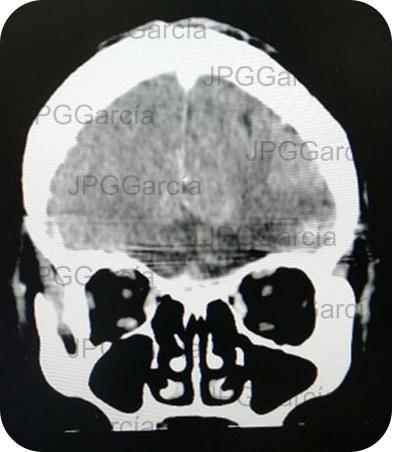

Resultado de tomografía craneal postquirúrgica en donde se observa drenaje del absceso cerebral